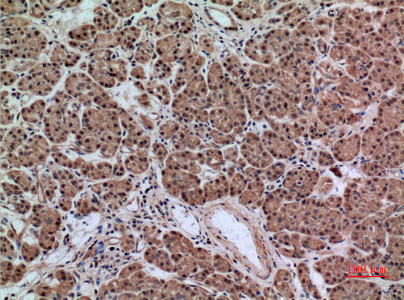

产品名称AACT Rabbit Polyclonal Antibody

推荐应用WB,IHC-P,IF-P,IF-F,IF-ICC,ELISA

免疫原The antiserum was produced against synthesized peptide derived from the Internal region of human SERPINA3. AA range:251-300

特异性AACT Polyclonal Antibody detects endogenous levels of AACT protein.

稀释度WB 1:500-1:2000, IHC-P 1:100-1:300, ELISA 1:20000, IF-P/IF-F/IF-ICC 1:50-200

背景介绍The protein encoded by this gene is a plasma protease inhibitor and member of the serine protease inhibitor class. Polymorphisms in this protein appear to be tissue specific and influence protease targeting. Variations in this protein's sequence have been implicated in Alzheimer's disease, and deficiency of this protein has been associated with liver disease. Mutations have been identified in patients with Parkinson disease and chronic obstructive pulmonary disease. [provided by RefSeq, Jul 2008],

组织表达Plasma. Synthesized in the liver. Like the related alpha-1-antitrypsin, its concentration increases in the acute phase of inflammation or infection. Found in the amyloid plaques from the hippocampus of Alzheimer disease brains.